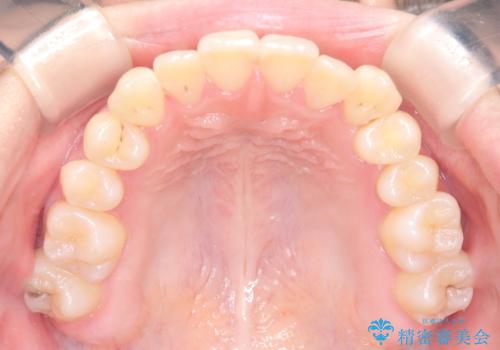

診査の結果、すでに下顎前歯の抜歯が行われていましたが、マウスピースの適合が著しく悪くなっており、歯が計画通りに動いていない状態でした。また、歯を支える骨の厚みや歯肉の薄さを考慮すると、このままマウスピースによる傾斜移動を続けるのは歯肉退縮(歯茎が下がること)のリスクが非常に高いと判断。

装置の変更と歯肉への配慮: ワイヤー矯正は歯の根(歯根)を平行に移動させる「歯体移動」を得意としています。本症例では、歯肉退縮を防ぐために、歯の傾きを精密にコントロールしながら抜歯スペースを閉じる必要がありました。ワイヤー装置を用いることで、インビザラインでは難しくなっていた三次元的な細かい調整を可能にしました。